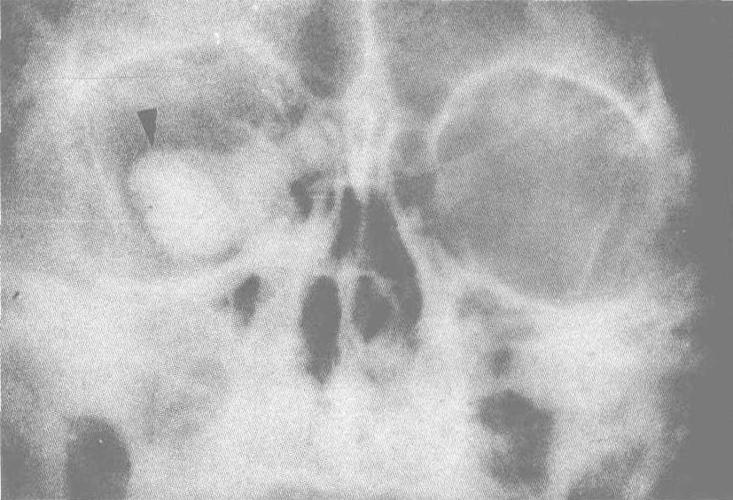

x线检查 多数正常,约1/4发现静脉石(图3),幼年开始患病者眶腔扩大及

静脉石11主要表现为点状的钙化,ct显示清晰,腹部平片